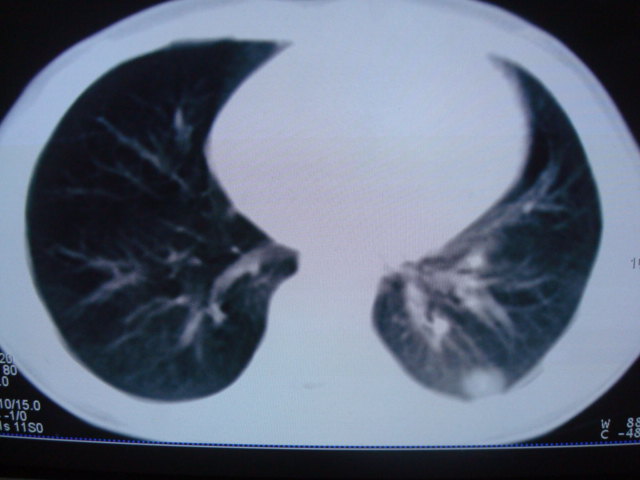

标题: PED0869:男,10岁,肺内多发结节+胸水 [打印本页]

标题: PED0869:男,10岁,肺内多发结节+胸水

男,10岁,左胸痛,发热轻,血象高。后到省级权威医院治疗,病情明显好转,结果几天后公布。老机器,图像质量差,见谅。

考虑血源性肺脓肿或韦氏肉芽肿

考虑血源性肺脓肿

血源性肺脓肿可能。

考虑血源性肺脓肿.支持!

考虑血源性肺脓肿.

考虑化脓性肺炎。